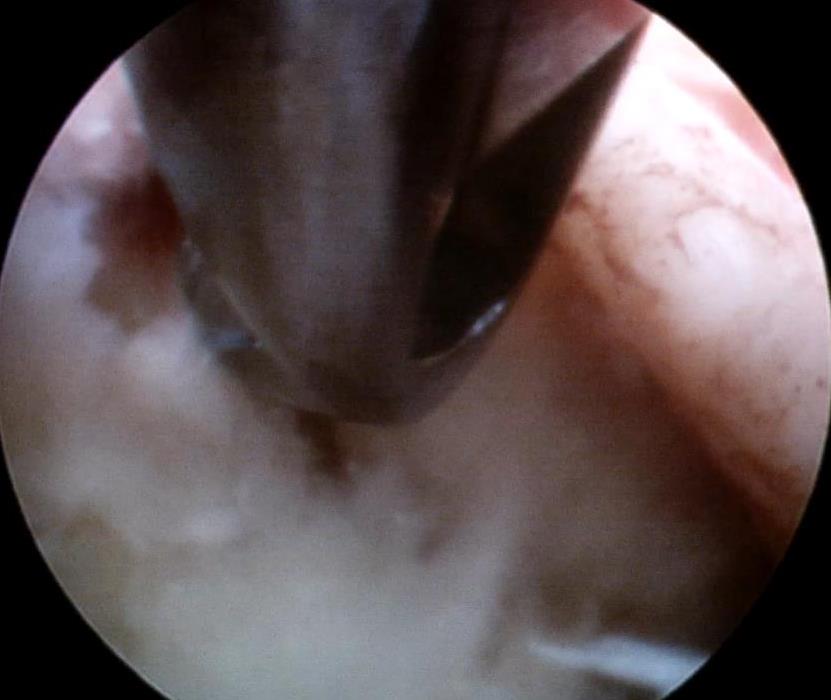

• 脊柱内镜侧后路联合减压术治疗腰神经根双卡综合征的临床疗效观察

2025, 31(12):25-32. DOI: 10.12235/E20250012

摘要 (122) HTML (46) PDF 10.14 M (90) 评论 (0) 收藏

摘要:目的 观察脊柱内镜侧后路联合减压术治疗腰神经根双卡综合征(DCS)的临床疗效、可行性、安全性和有效性。方法 回顾性分析2018年9月-2023年9月于该院就诊的50例腰椎退行性病变致腰神经根DCS患者的临床资料,根据手术方法不同,将患者分为观察组(37例)和对照组(13例)。观察组行脊柱内镜侧后路联合减压术治疗,对照组行非手术治疗。比较两组患者治疗前、治疗后1周、治疗后3个月、治疗后6个月和治疗后12个月的疼痛视觉模拟评分法(VAS)评分、Oswestry功能障碍指数(ODI)和日本骨科协会(JOA)评分。末次随访时,采用改良Macnab标准,评估临床疗效;采用腰椎MRI检查,评估椎间隙高度和椎间盘退变改良Pfirrmann分级。比较两组患者治疗的安全性(包括:并发症发生情况、复发情况和转手术治疗情况)。结果 50例患者均顺利完成治疗。两组患者术后VAS评分和ODI呈下降趋势,JOA评分呈升高趋势,观察组术后各时点VAS评分和ODI明显低于术前,且明显低于对照组,术后各时点JOA评分明显高于术前,且明显高于对照组,差异均有统计学意义(P < 0.05);观察组优良率为86.49%,明显高于对照组的76.92%,差异有统计学意义(P < 0.05);两组患者末次随访时,椎间隙高度和椎间盘退变Pfirrmann分级比较,差异均无统计学意义(P > 0.05)。两组患者围手术期均未出现神经损伤和脑脊液漏等严重并发症,观察组术后1例出现下肢放射性疼痛;观察组1例术后3个月出现腰椎间盘再突出;对照组有3例转手术治疗。结论 与非手术治疗相比,脊柱内镜侧后路联合减压术可更为安全、有效地缓解腰神经根DCS患者的疼痛,改善下肢功能,且早、中期临床疗效好。值得临床推广应用。